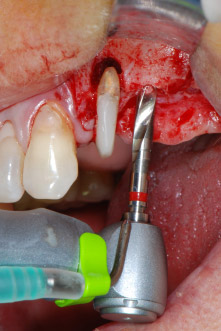

implant motor

Fig. 8: Rotary preparation of the implant bed short of the floor of the maxillary sinus at position 25, carried out with an updated implant motor.

Implant beds were prepared at sites 25 and 26 with rotary instruments, used in a contra-angle handpiece with a 20 : 1 transmission ratio with an updated powerful implant motor (Implantmed, W&H) (Fig. 8).

The final preparation next to the sinus was again carried out with a piezoelectric instrument (Piezomed, insert S2).